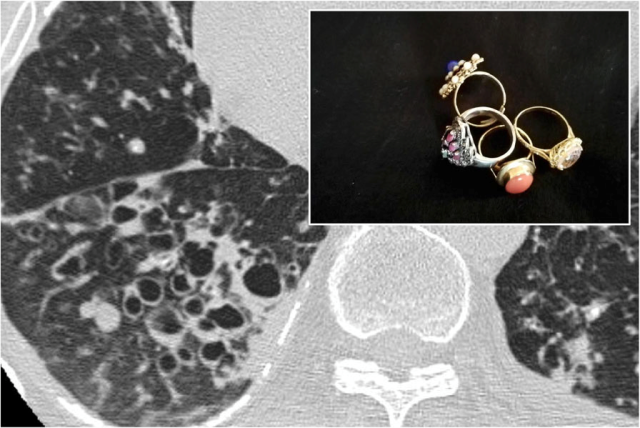

例如,以下是一位患有囊性纤维化的年轻患者的胸部CT,可见多发支气管扩张和印戒征[5]。

囊性纤维化患者的胸部CT:印戒征[5]

在Wang L曾报道一例慢性咳嗽、咳痰10年的38岁女性,胸部CT示弥漫性支气管扩张(左肺上叶、舌叶和左肺下叶印戒征),左肺下叶支气管狭窄伴多发边缘清晰的结节影。支气管镜和病理检查证实为异物吸入,医生经询问病史发现,过去10年内患者经常在睡觉时口含黄连以治疗味觉异常,由此证实为黄连吸入后继发的支气管扩张症[6]。

异物吸入并发支气管扩张症的38岁女性:胸部CT示印戒征和多发结节影[6]